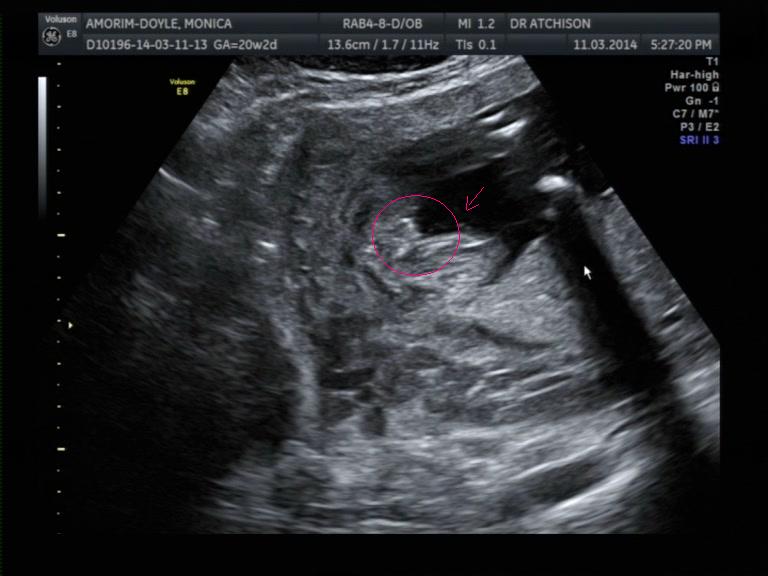

Cheeky because she was upside down and made it hard and unreliable to guess, YET I only got girl guesses. This is her 12+3 days nub and the last a potty shot at 20 weeks.